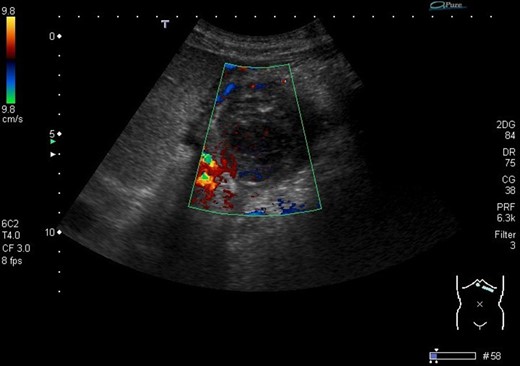

He presented to the local tertiary referral centre complaining of chest pain and the normal ECG, cardiac markers and chest X-ray suggested a non-cardiac cause for the pain. He remained haemodinamically stable and was further investigated with an abdominal ultrasound (USS) and a contrast enhanced computed tomography (CT). The latter demonstrated a 5 × 3.8 cm2 pseudoaneurysm posterior to the stomach and superior to the body of the pancreas but of unclear origin. It also showed a large subcapsular splenic haematoma measuring 10.8 × 7.7 cm2 and a perisplenic collection (Fig. 1).

CT abdomen image shows flow in pseudoaneurysm (arrow) posterior to the stomach and the subcapsular splenic haematoma.